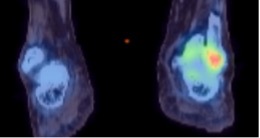

PET (Positron emission tomography)

Pre-treatment PET-CT activity of giant cell tumour of the calcaneum showing marked peripheral FDG uptake

Post denosumab treatment PET-CT of the same lesion showing tumour response with reduced FDG uptake

Generation of PET image

A positron-emitting radiopharmaceutical is injected intravenously, and the scanner detects the quantity and pattern of accumulation in the body.

A PET scan can also be combined with CT, and in some centres with MR, to improve disease localisation.

F-18 Fluorodeoxyglucose (FDG)-PET scan localises areas of maximal glucose activity in the body. Tumour or infection are usually FDG-PET avid.

F-18 Sodium Fluoride-PET (NaF)-PET scan uses a radiotracer which localises areas of osteoblastic activity and is therefore more specific for bone pathologies.